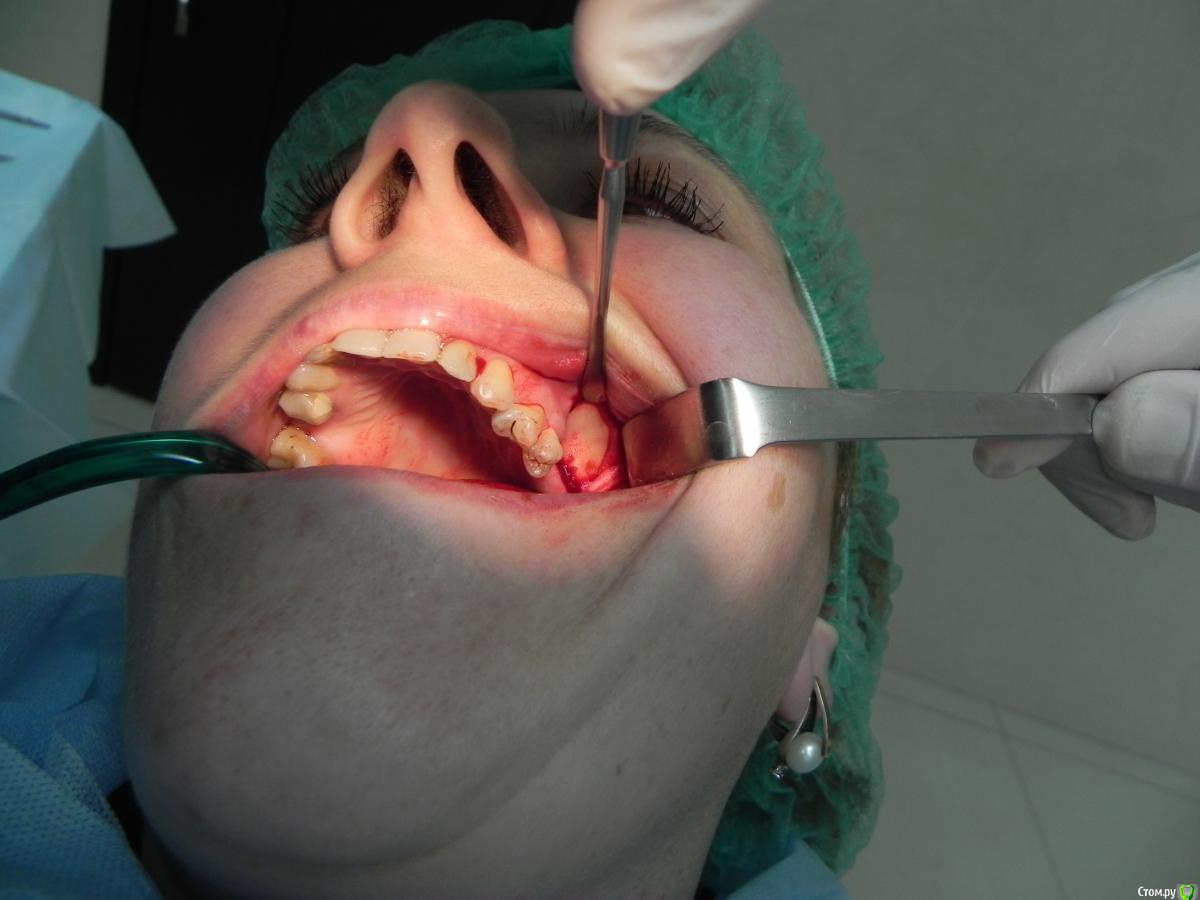

Kostoprav Опубликовано 7 августа, 2015 Поделиться Опубликовано 7 августа, 2015 доступпрепаровка шаровидной костной фрезойпри отслаивании мембраны образовалась маленькая перфа перфорацию" проклеил" коллагеновой мембранойпод мембрану внесен материалмембрана на окноготово может кому из начинающих этот пост полезен будет 1 Ссылка на комментарий

Alexey Doc Опубликовано 7 августа, 2015 Поделиться Опубликовано 7 августа, 2015 Аккуратная работа!Пару вопросов;Имплантация планируется только в области 6-го?Рентген-снимки есть какие нибудь для наглядности объема аугментации?В дренажах смысла не вижу 1 Ссылка на комментарий

Kostoprav Опубликовано 7 августа, 2015 Автор Поделиться Опубликовано 7 августа, 2015 Аккуратная работа!Пару вопросов;Имплантация планируется только в области 6-го?Рентген-снимки есть какие нибудь для наглядности объема аугментации?В дренажах смысла не вижуспасибона 7 тоже рассчитываюпостараюсь выложить кт сканыну вреда от него точно не будет Ссылка на комментарий